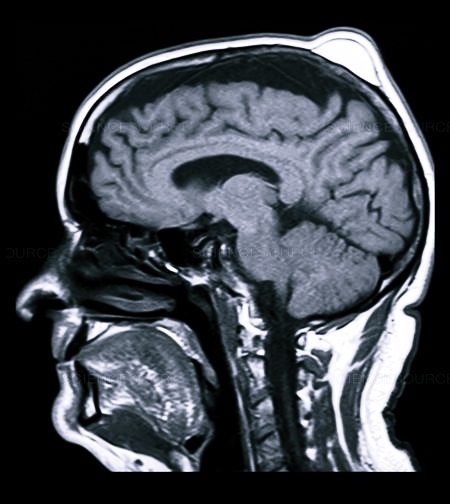

- МРТ или КТ;

При проявлении вышеуказанных симптомов необходимо сразу обратиться к врачу, чтобы удостовериться в отсутствии тяжелого повреждения головного мозга или кровоизлияния. Для того чтобы определить, насколько серьезна травма, необходимо пройти МРТ или КТ.

При черепно-мозговой травме используют рентген, МРТ и КТ, нередко проводится ангиография (исследование сосудов мозга с введением контрастных препаратов).

- Магнитно-резонансная томография.